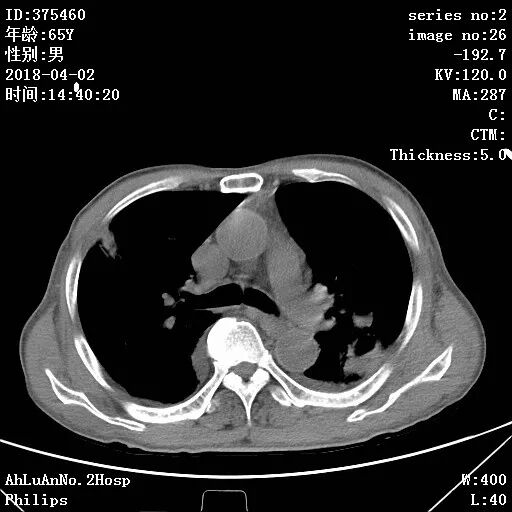

患者男,65岁,因“咳嗽、咳痰1月余,发热1周”入院。

两肺可见多发斑片状及气囊样阴影,部分气囊样影内可见气液平面,两侧胸膜腔可见少量液性密度影聚集。

结果:金黄色葡萄球菌肺炎

显示,白细胞计数和中性粒细胞百分比升高,可有核左移及中毒颗粒。本病的胸部X线特征常表现为肺段或肺叶实变,或呈小叶样浸润,其中有单个或多发的液气囊腔。

X线阴影的易变性是本病的另一重要特征,其常表现为一处炎性浸润消失而在另一处出现新的病灶,或很小的单一病灶发展为大片阴影。